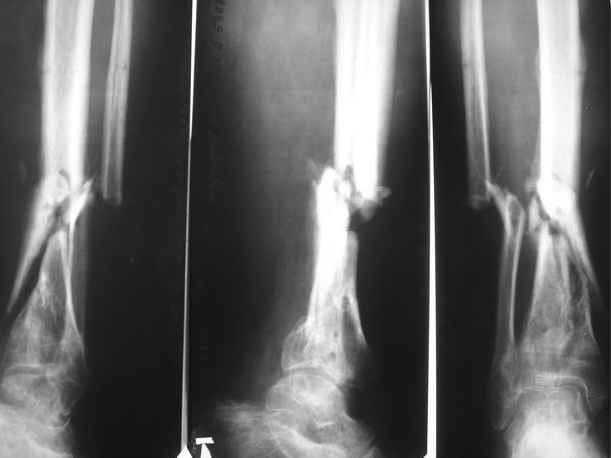

Пациент 35 лет, травма в декабре 2007 г. Открытый оскольчатый перелом костей левой голени в нижней трети со смещением отломков. Травма в результате ДТП. В этот же день выполнена ПХО открытого перелома костей левой голени, скелетное вытяжение. На 3 день ЧКДО с учетом повреждения мягких тканей. Посттравматический период осложнился обширным циркулярным некрозом кожи. Через этапные некроэктомии, и свободную кожную пластику раны зажили вторичным натяжением. По заживлении мягких тканей перемонтаж аппарата. Выписан на амбулаторное лечение. В августе 2008 г. из за выраженного воспаления в местах выхода спиц, аппарат демонтирован. Явления воспаления купированы. Данных за остеомиелит не получено. На данный момент имеем: ложный сустав левой большеберцовой кости в нижней трети. Укорочение левой нижней конечности на 3 см. Комбинированная контрактура левого голеностопного сустава. Клинически – патологическая подвижность в области перелома. Лабораторные показатели в пределах нормы. Местно воспалительных явлений мягких тканей нет.

1. Вариант № 1(основной) – в два этапа. 1. Наложить спице-стержневой аппарат, за 5 – 7 – 10 дней устранить смещение отломков (восстановить ось большеберцовой кости). 2 этап закрытый блокированный остеосинтез цельным гвоздем диметра 10 – 11 мм для низких переломов голени (Эксперт, Мастер…). Сначала в статику на 2-3 недели, затем динамизацию.

1.Достаточна ли длина дистального отломка для жесткой фиксации на гвозде ( как минимум на 3 винтах)?

3. Возможно ли выполнить закрытый блокируемый остеосинтез без предварительного наложения КДА?